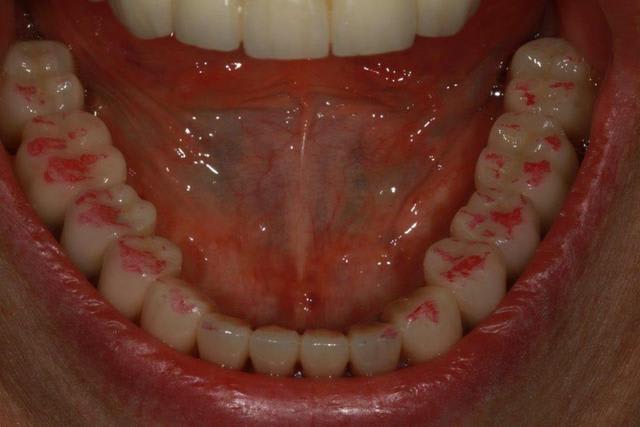

Enlaye, j'ai fait un contrôle avec papier rouge (épais)

ton avis?

Photo 1 dents serrées occlusion sans glissement

Photo 2 le bas après papier rouge

Photo 3 le haut après papier rouge

Photo 4 le bas après retouche et papier rouge

Photo 5 le haut après retouche et papier rouge

Photo 6 latéralité gauche

Photo 7 latéralité droite

La sensation de "rigidité" pour le maxillaire sup s’estompe, la patiente s'approprie ses nouvelles prothèses.

le petit "truc" concernant l'implant semble fonctionner...à merveille.